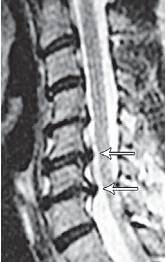

МРТ № 39

На рентгенограмме № 6 поясничного отдела позвоночника выраженный остеофитоз, спондилёз третьей степени, что также хорошо видно на МРТ № 39 поясничного отдела позвоночника